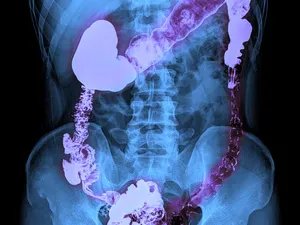

结肠为介于盲肠和直肠之间的部分,按其所在位置和形态,又分为升结肠、横结肠、降结肠和乙状结肠四部分。

(1)升结肠 长约15cm,是盲肠向上延续部分,自右髂窝沿腹后壁的右侧上升,至肝下方向左弯形成结肠右曲,移行于横结肠。升结肠后面借结缔组织附贴于腹后壁,故活动性较小。

(2)横结肠 长约50cm,起自结肠右曲,向左横行至脾处再向下弯成结肠左曲 ,移行于降结肠。横结肠全部被腹膜包被,并借横结肠系膜连于腹后壁,其中部下垂,活动性较大。

(3)降结肠 长约20cm,从结肠左曲开始,沿腹后壁的左侧下降,至左髂嵴处移行于乙状结肠。降结肠后面借结缔组织附贴于腹后壁,所以活动性也小。

(4)乙状结肠 长约40-45cm,平左髂嵴处接续降结肠,呈“乙”字形弯曲,至第3骶椎前面移行为于直肠。空虚时,其前面常被小肠 遮盖,当充盈扩张时,在左髂窝可触及。乙状结肠全部被腹膜包被,并借乙状结肠系膜连于左髂窝和小骨盆后壁,其活动性也大。